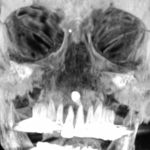

Inverted Supernumerary Tooth

3D volume bony reconstruction of an incidentally detected supernumerary tooth in the setting of trauma (MVC). Patient...